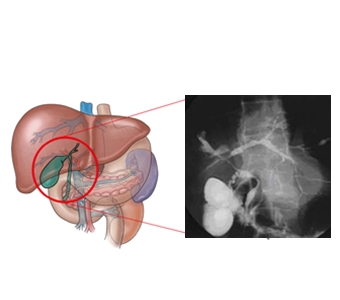

간문부 담관암(Klatskin's tumor)

- 관련질환

-

총담관 낭,

담석,

경화성 담관염,

총담관 담석,

간디스토마,

궤양성 대장염

- 진료과

소화기내과,

종양내과,

방사선종양학과,

간담도췌외과,

간이식ㆍ간담도외과